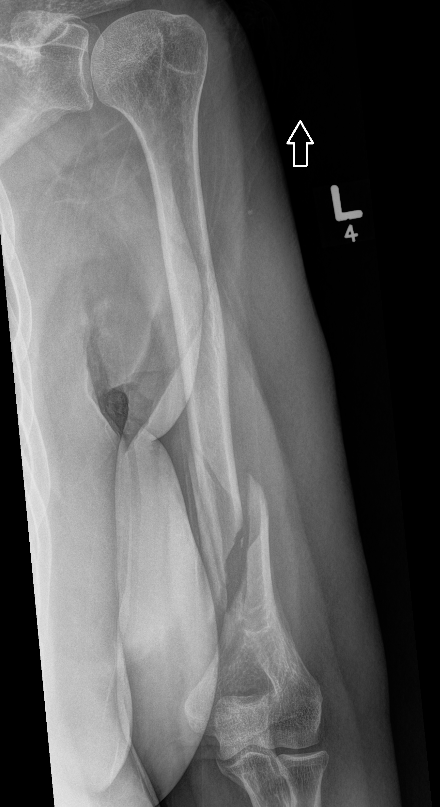

Union of a midshaft humerus fracture treated nonoperatively

Union of distal humerus fracture treated nonoperatively